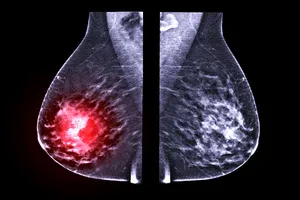

이를 통해 결절이 양성인지 악성인지, 악성일 경우 어떤 종류의 암인지 정확하게 판단할 수 있습니다. 유방암은 조기에 발견할수록 치료 효과가 좋습니다. 조직검사를 통해 유방암을 조기에 발견하면 완치율을 높일 수 있습니다.

암세포가 발견된 경우 악성으로 판정됩니다. 악성 종양으로 진단되면 암의 종류, 전이 여부 등을 확인하기 위한 추가적인 검사를 받아야 합니다.